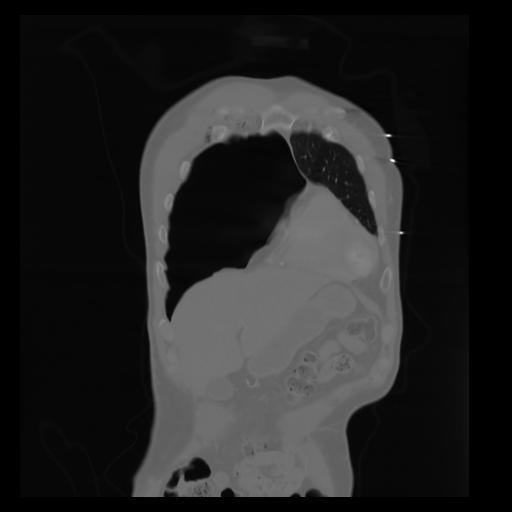

29 CUERPO,CE,Coronal,3.000,CUERPO,Coronal,